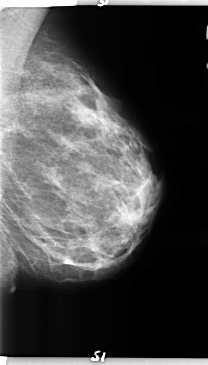

B_3157_1.LEFT_MLO

LEFT_MLO LINES 4736 PIXELS_PER_LINE 2704 BITS_PER_PIXEL 12 RESOLUTION 50 NON_OVERLAY